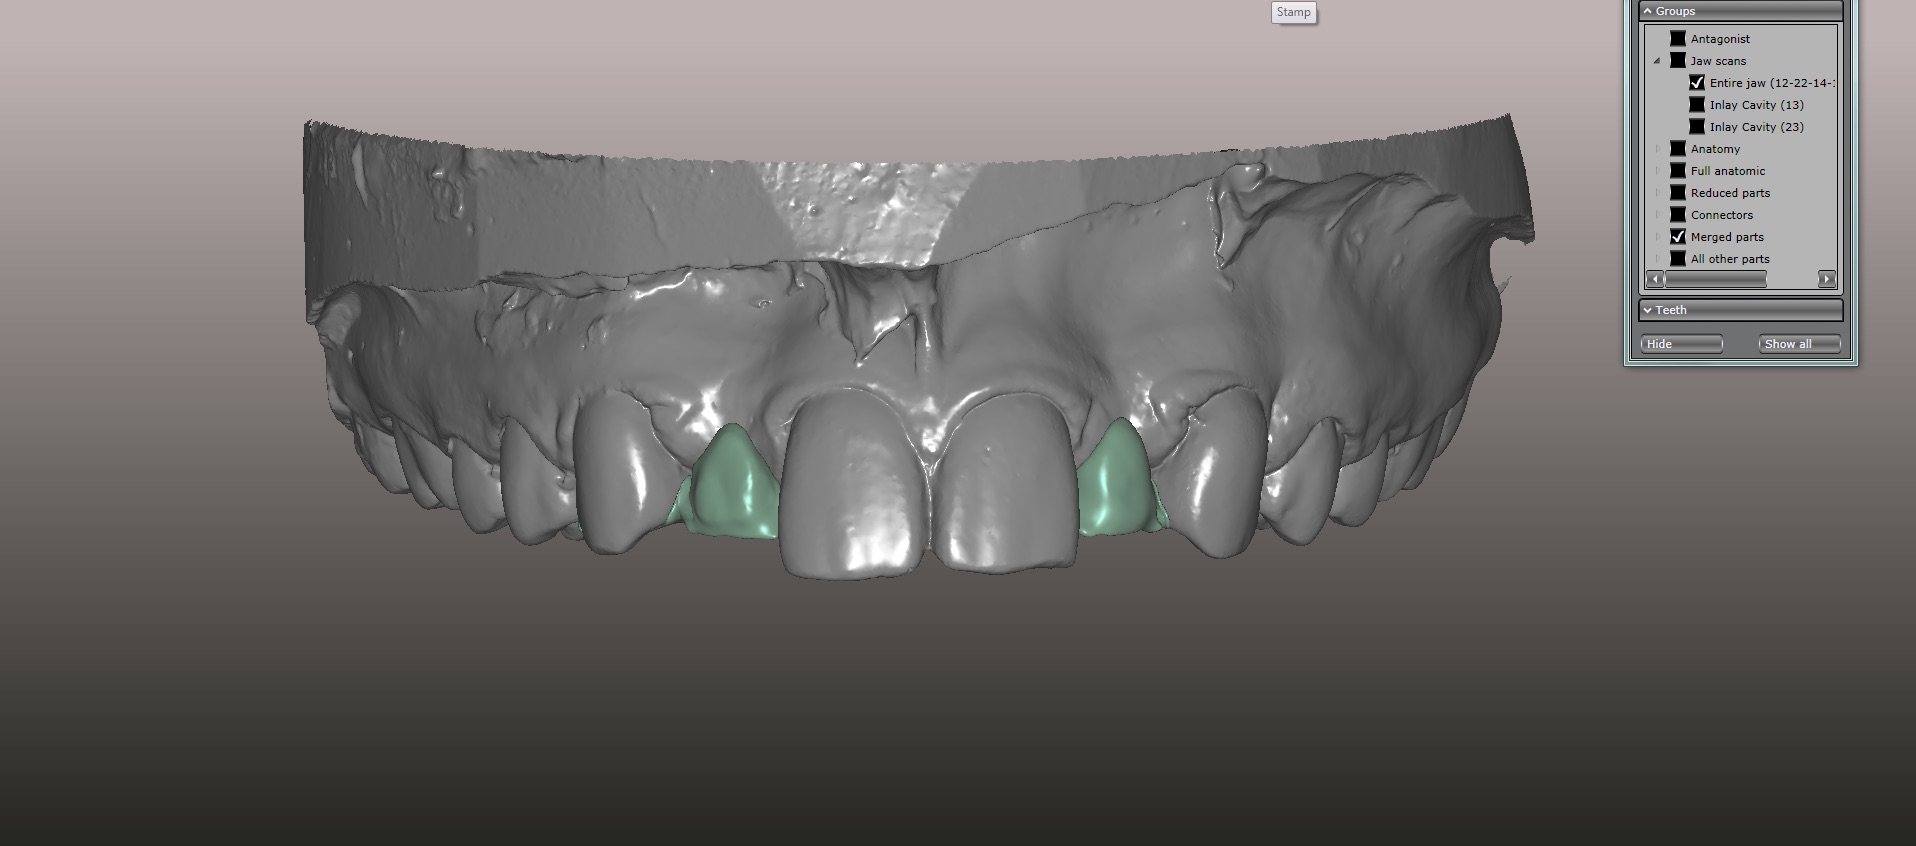

(16.) Virtual design of anatomic form generated from a virtual library of tooth forms, which was used to fabricate temporary PMMA resin-bonded bridges.

Figure 16

An approach utilizing CAD/CAM was employed to fabricate an accurate fitting, retentive, and esthetic ceramic single-wing resin-bonded bridge. Impressions were taken of the patient and scanned in the laboratory using maximum intensity projection. The scanned models were then used to design the final prosthetic frames utilizing EXOCAD software. The retainer positions and extensions were designed on the models based on the occlusal clearance (Figure 15). Next, the replacement tooth forms were chosen from a virtual library (Figure 16), and try-in PMMA bridge prototypes were milled in Primotec USA PMMA. This allowed for try-in of the design, adjustment of the contacts, and intraoral evaluation of the ridge contact (Figure 17). Once tried and idealized for both fit and occlusion, the design was sent back to the lab to rescan. Utilizing the software, a cut back was made on the lateral incisor (Figure 18), and a 0.3mm space was also virtually designed on the internal surface of the retainer wing to allow layering with feldspathic ceramic (Figure 19). The 0.2 mm internal edge of the wing was designed to be left intact to allow for precise seating and verification of fit on the model. After the frame was milled in zirconia (Zirconzahn, Prettau), it was verified on the model, and high fusing margin porcelain (Noritake CZR) was mixed with a clear utility wax and applied to the internal 0.3 mm depression. This was baked in the oven at a high temperature, allowing the wax to burn out and leaving the feldspathic ceramic fused to the internal surface of the retainer. Once cooled, this was checked for precise fitting on the model and adjustments were made to ensure full seating.